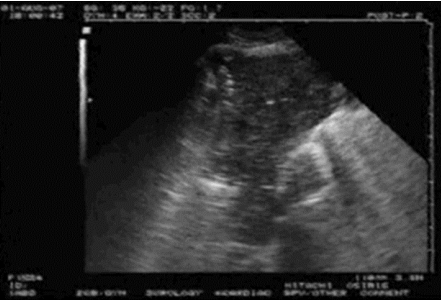

A线的出现代表胸膜线以下含气良好。此时针对呼吸困难的病因,就应考虑是否存在气道病变或血管病变。需要行下肢血管彩超进一步筛查,如果发现血管中有回声团(图2),考虑存在下肢静脉血栓,此时需要警惕肺栓塞的可能。如有条件,可行肺动脉CTA检查;如无条件,可检查凝血功能、心肌标志物、心脏彩超等进行筛查。如果下肢血管彩超没有问题,就要加做PLAPS点(图3),即最常出现胸腔积液、炎性变之处,若此处正常,考虑可能是气道疾病,若出现胸膜下斑片影、实变影,考虑肺炎可能。(3)不论有无胸膜滑动征,如果在患者一侧以A线为主,另一侧以B线为主(AB profile)(图4),考虑为肺炎;若超声有实变征象(C profile)(图5),则更支持肺炎的诊断。图4 一侧为A线,另一侧为B线(AB profile)(4)如果胸膜滑动征消失,且观察到B线(B’ profile)(图6),此种情况考虑肺炎。(5)如果胸膜滑动征消失,且双肺表现为A线,称为A'profile。